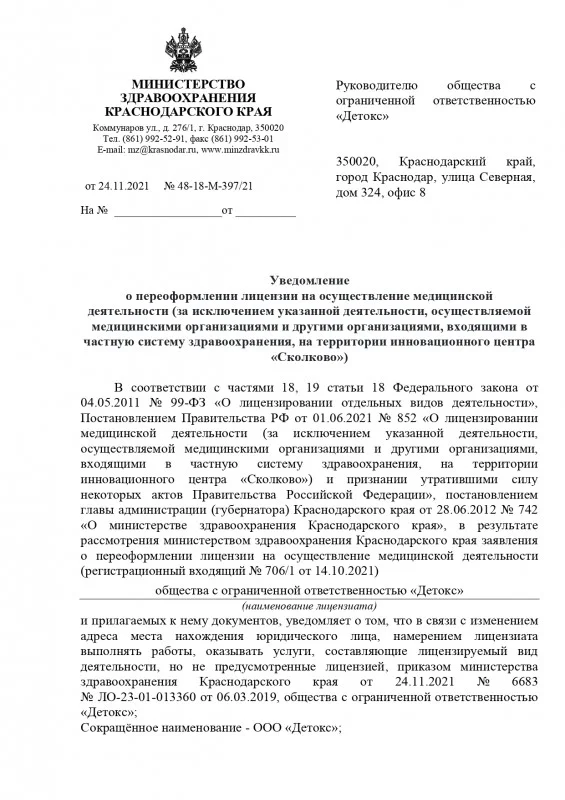

Лицензия на осуществление медицинской деятельности

Лицензия на осуществление медицинской деятельности

Лицензия на осуществление медицинской деятельности

Лицензия на осуществление медицинской деятельности

Лицензия на осуществление медицинской деятельности

Лицензия на осуществление медицинской деятельности

Лицензия на осуществление медицинской деятельности

Лицензия на осуществление медицинской деятельности